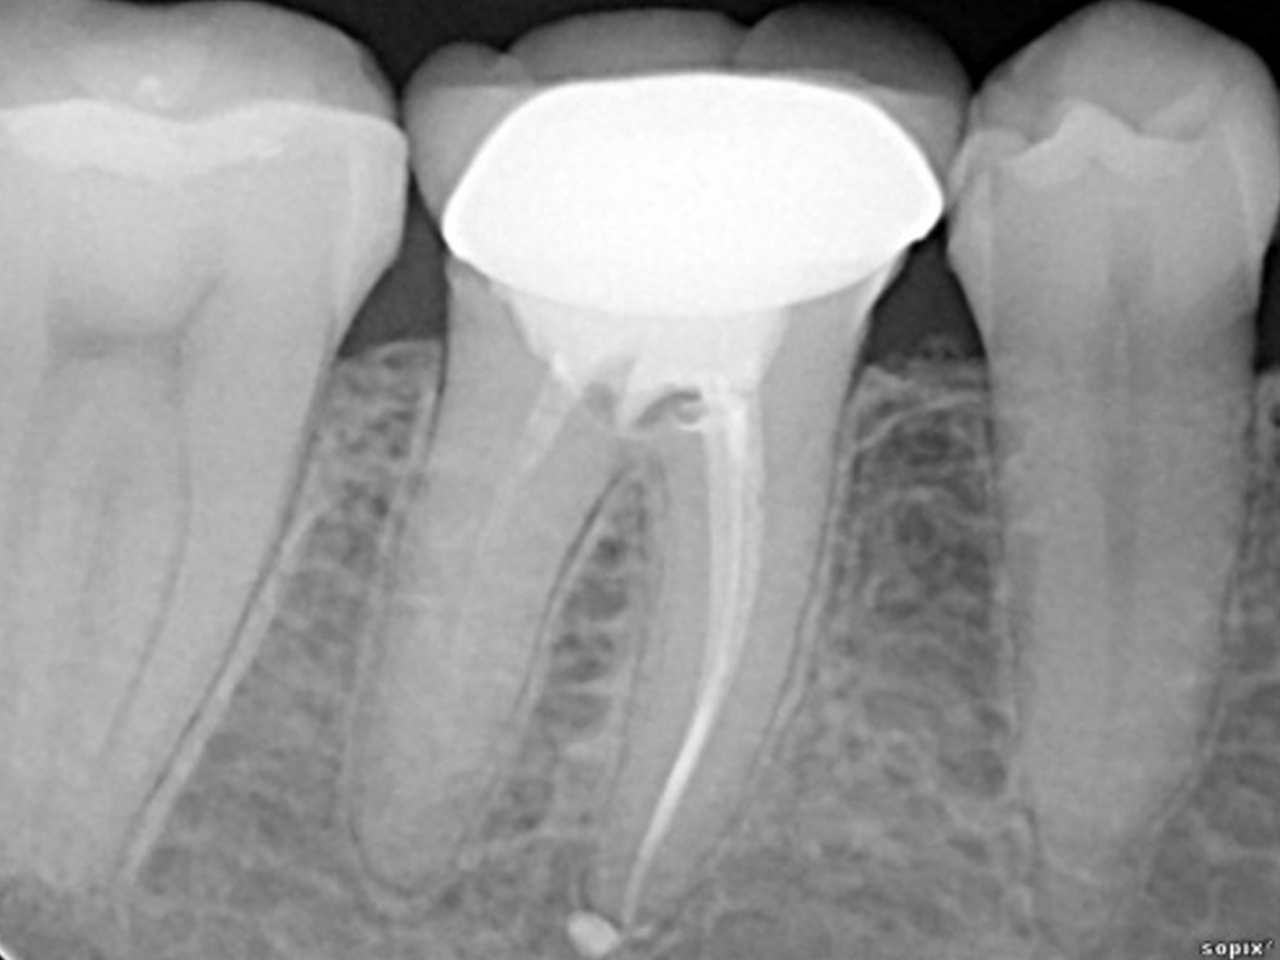

Качество изображения

От качества изображения напрямую зависит точность диагностики и необходимость повторных исследований.

Ключевые параметры:

• Разрешение (измеряется в парах линий/мм): чем выше, тем детальнее изображение.

• Чувствительность матрицы: влияет на то, насколько хорошо датчик работает при минимальной дозе излучения.

• Алгоритмы обработки: современные программы улучшают контраст и убирают шум, что особенно важно при эндодонтических и пародонтологических исследованиях.

Также необходимо правильно настроить время экспозиции на рентген-аппарате, так как разные датчики имеют разную чувствительность. Оптимальное решение — использовать комплект оборудования одного производителя либо подобрать совместимые устройства с помощью специалистов.